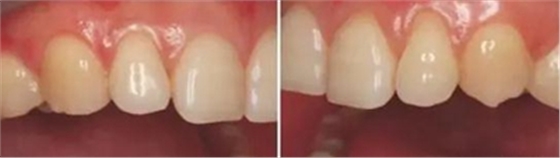

上下前牙正面影像

構圖包含4-6顆前牙,中切牙為對焦中心

采用黑背景

拍攝比例:1:1.8,光圈f38,快門速度1/125,閃光強度M/4